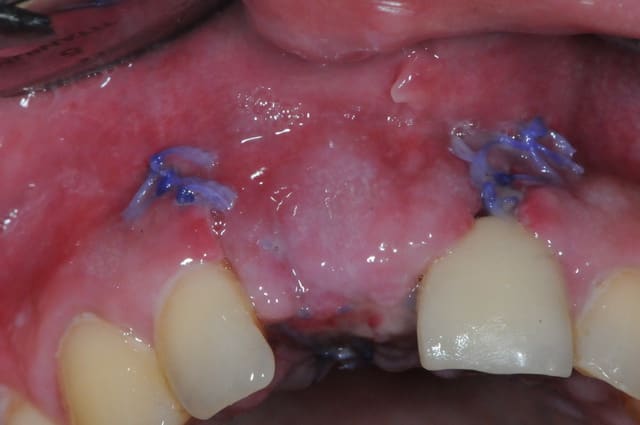

> Ci joint cas avec biobank, très bonne stabilité et consistance a la réouverture

> a 9 mois.

> Pour ce qui est du déficit en GA, j'avais greffé a 5 mois sur la greffe biobank,

> et la vascularisation du greffon osseux n’étant pas abondante, la cicatrisation

> a été difficile.

>

> je dois reintervenir juste en vestibulaire de la 46 qui manque de GA.

j'ai retrouvé, mais c'est le correspondant qui à posé l'implant et les photos sont pas top :(

ceux sont les photos du correspondant .